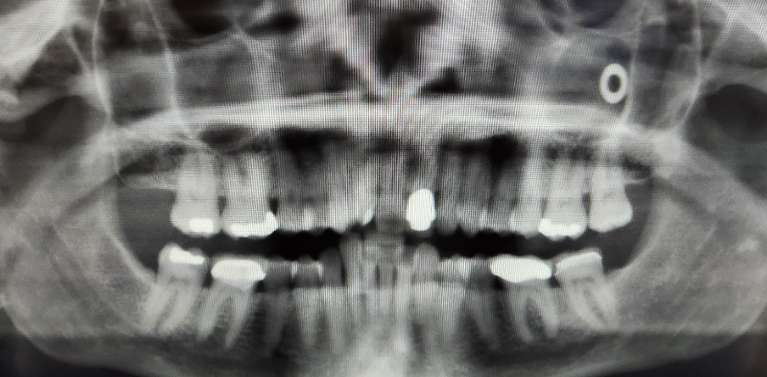

Panoramic X-Rays

Panoramic x-rays are another useful diagnostic tool that allows Dr. Bellegarrigue to observe your entire oral structure—teeth, gums, soft tissue, hard tissue, bone, neck, and more. The images are two-dimensional and provide a flat image that shows all the vital foundations of your smile.

Panoramic x-rays show Dr. Bellegarrigue a comprehensive image of your head and neck, which can help him diagnose complicated oral health issues, including bone or soft tissue abnormalities.

Using panoramic x-rays helps us diagnose:

- Tooth and gum infections

- Fractured teeth

- Tooth impaction

- Cysts

- Oral abnormalities

- Bone health

- Tumors

- Periodontal disease

- TMJ

Panoramic x-rays can also help Dr. Bellegarrigue with orthodontic, cosmetic, or restorative treatments like braces, dental implants, dental bridges, and dentures.